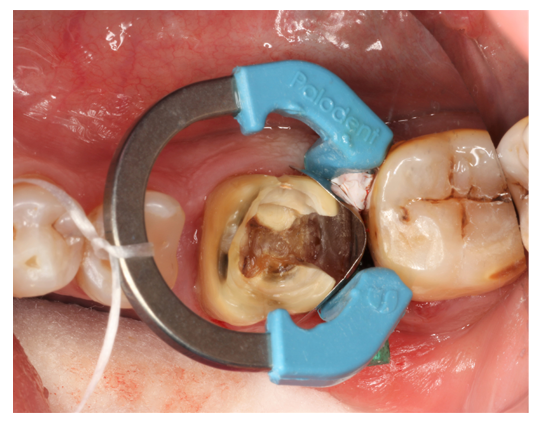

Der Keil wurde nur vorsichtig nach interdental eingebracht, um die Matrize nicht zu verformen. Die Separation konnte anschließend durch Anlage eines Separationsringes erreicht werden. Da eine Kofferdamisolation nicht möglich war, wurde der Ring zusätzlich mit Zahnseide gesichert.

Abb. 3: Isolation des deutlich subgingivalen Defektes an Zahn 36 nach Kariesexkavation. Neben einer federharten Teilmatrize mit subgingivaler Lasche wurden Teflonband, ein interdentalkeil sowie ein mit Zahnseide gesicherter Separationsring zur Kontaminationskontrolle eingesetzt. | Foto: Anne-Katrin Lührs

Nach adhäsiver Vorbehandlung erfolgte der alleinige Aufbau der distalen Randleiste unter gleichzeitigem Erhalt der Zugangskavität zum Wurzelkanalsystem (Abb. 4). Im Rahmen der Kontaminationskontrolle wurde auf den Einsatz von Adstringentien verzichtet.

Abb. 4: Zustand nach Aufbau der distalen Randleiste 36 mittels Bulk-Fill-Flowable zur Restauration zervikal liegender Defektanteile in Kombination mit einem Hybridkomposit nach Entfernung des Separationsringes. | Foto: Anne-Katrin Lührs